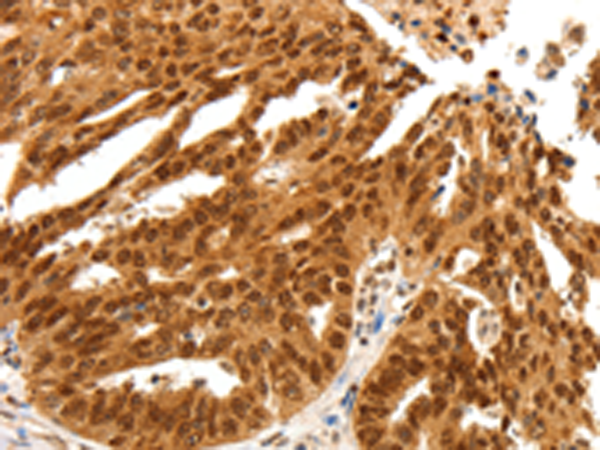

IHC positive control: |

Human ovarian cancer and human colon cancer |

IHC Recommend dilution: |

25-100 |